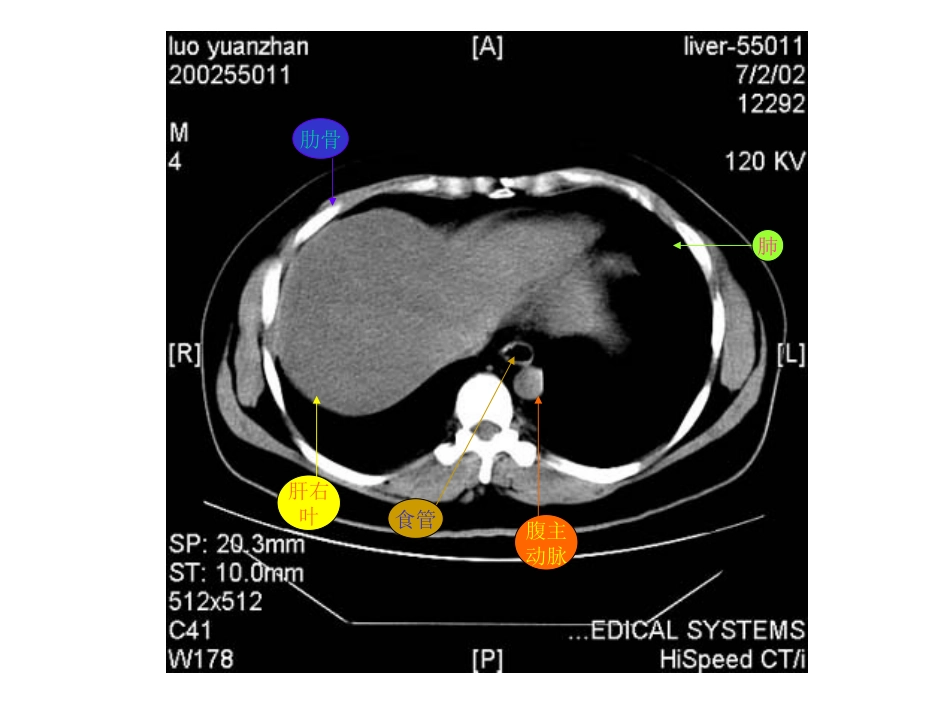

肝右叶横膈肺胸椎脊髓腹主动脉食管肋骨肋骨肝右叶腹主动脉食管肺肝左叶肝右叶腹主动脉胃脾肝尾叶肝右叶尾叶膈脚脾门静脉肝左叶胃肝右叶膈脚腹主动脉脾胆囊胃肝右叶下腔静脉胰腺脾胃腹主动脉肝右叶心脏腹主动脉下腔静脉脊髓食管肺肝左叶肝右叶腹主动脉下腔静脉胃脾脊髓肝左叶及肝左动脉肝右叶及肝右动脉腹主动脉下腔静脉胃脾肝尾叶肝右叶下腔静脉腹主动脉胃脾膈脚肝静脉下腔静脉腹主动脉食道肝右叶下腔静脉肝右叶肝静脉肝左叶腹主动脉胃脾肝尾叶肝右叶下腔静脉腹主动脉门静脉主干肝左叶胃脾肝右叶下腔静脉门静脉腹主动脉膈脚脾胃肝血管瘤CT平扫呈低密度灶,密度均匀,边缘较清。肝血管瘤静脉注入造影剂后CT扫描,动脉期示:病灶由边缘向中心结节状强化,逐渐填满,其密度与同层腹主动脉相似。腹主动脉肾肝血管瘤静脉期示病灶进一步强化填充,呈密度较均的高密度灶,显示更清楚。肝血管瘤2分钟后,平衡期CT扫描示病灶仍呈较高密度,显示清楚,表现为“早出晚归”征肝血管瘤CT平扫示肝脏左右叶普遍增大。静脉注入造影剂后CT扫描,静脉期示肝实质呈不均匀强化。门静脉肝硬化:CT平扫示肝脏左右叶体积缩小,边缘欠平整,肝裂增宽肝裂增宽肝硬化并门静脉高压,静脉注入造影剂后静脉期CT扫描示:脾门静脉曲张。脾门静脉曲张脾肝右叶肝左叶肝癌CT平扫示:肝脏体积明显增大,边缘不平整,肝实质密度不均,内见结节状、团块状低密度癌灶,边缘模糊,密度不均。肝右叶巨大癌灶肝内结节状癌灶静脉注入造影剂后CT扫描,动脉期示:肝内癌灶不均匀增强,密度增高,其内见肿瘤坏死部分不强化,呈更低密度。癌灶增强,密度增高瘤内坏死部分呈更低密度静脉早显肿瘤血管肿瘤假包膜静脉注入造影剂后CT扫描,静脉期示下腔静脉内癌栓呈低密度充盈缺损表现。肝右叶癌灶腹主动脉静脉注入造影剂后CT扫描,静脉期示:由于造影剂洗脱,肿瘤呈较低密度。本例见癌肿侵犯门静脉,门脉左支受压变形,门脉右支未见显影。门静脉左支受压变形肝内癌灶静脉注入造影剂后CT扫描,平衡期示:肝内癌灶随造影剂进一步洗脱呈低密度表现。本例门静脉左支内还可见稍低密度癌栓。门静脉左支及其内癌栓肝内癌灶胆囊体积缩小,胆囊壁稍厚。肾胰肝肾静脉腹主动脉慢性胆囊炎CT平扫示:胆囊体积缩小,胆囊后壁见一类椭圆形高密度结石胆囊结石腹水肝胰肠管脾腹水肾正常胰腺CT平扫胰腺体、尾部胆囊肝右叶脾肠管下腔静脉膈脚腹主动脉正常胰腺CT平扫肝右叶胰头肠管肾腹主动脉下腔静脉静脉注入造影剂后,正常胰腺CT对比增强扫描胆囊肝右叶下腔静脉胰体胰尾脾肾肠管脾静脉静脉注入造影剂后,正常胰腺CT对比增强扫描胰头下腔静脉肝右叶腹主动脉肾肠管脾静脉脾急性单纯性胰腺炎CT平扫胰腺肝脾左肾下腔静脉腹主动脉胃急性单纯性胰腺炎CT平扫胰腺脾右肾肝下腔静脉腹主动脉胆囊胃急性单纯性胰腺炎CT平扫胰头胃肝胆囊脾左肾下腔静脉腹主动脉肠管急性单纯性胰腺炎CT对比增强扫描胰腺胃胆囊肝下腔静脉腹主动脉脾静脉左肾脾急性单纯性胰腺炎CT对比增强扫描腹主动脉脾静脉下腔静脉胰头肝胆囊胃左肾脾肠管急性渗出性胰腺炎CT平扫胰腺胃肝脾右肾下腔静脉腹主动脉急性渗出性胰腺炎CT平扫胰腺胃肝脾腹主动脉下腔静脉右肾肾前筋膜增厚胆囊急性渗出性胰腺炎CT平扫胰腺胃胆囊肝右肾下腔静脉腹主动脉肾前筋膜增厚左肾脾慢性胰腺炎CT增强扫描示:胰管扩张胰腺扩张胰管胃胆囊增大肝右肾右肾静脉腹主动脉左肾左肾静脉脾胰腺体积缩小胰腺胃脾左肾肝右叶肝左叶下腔静脉腹主动脉